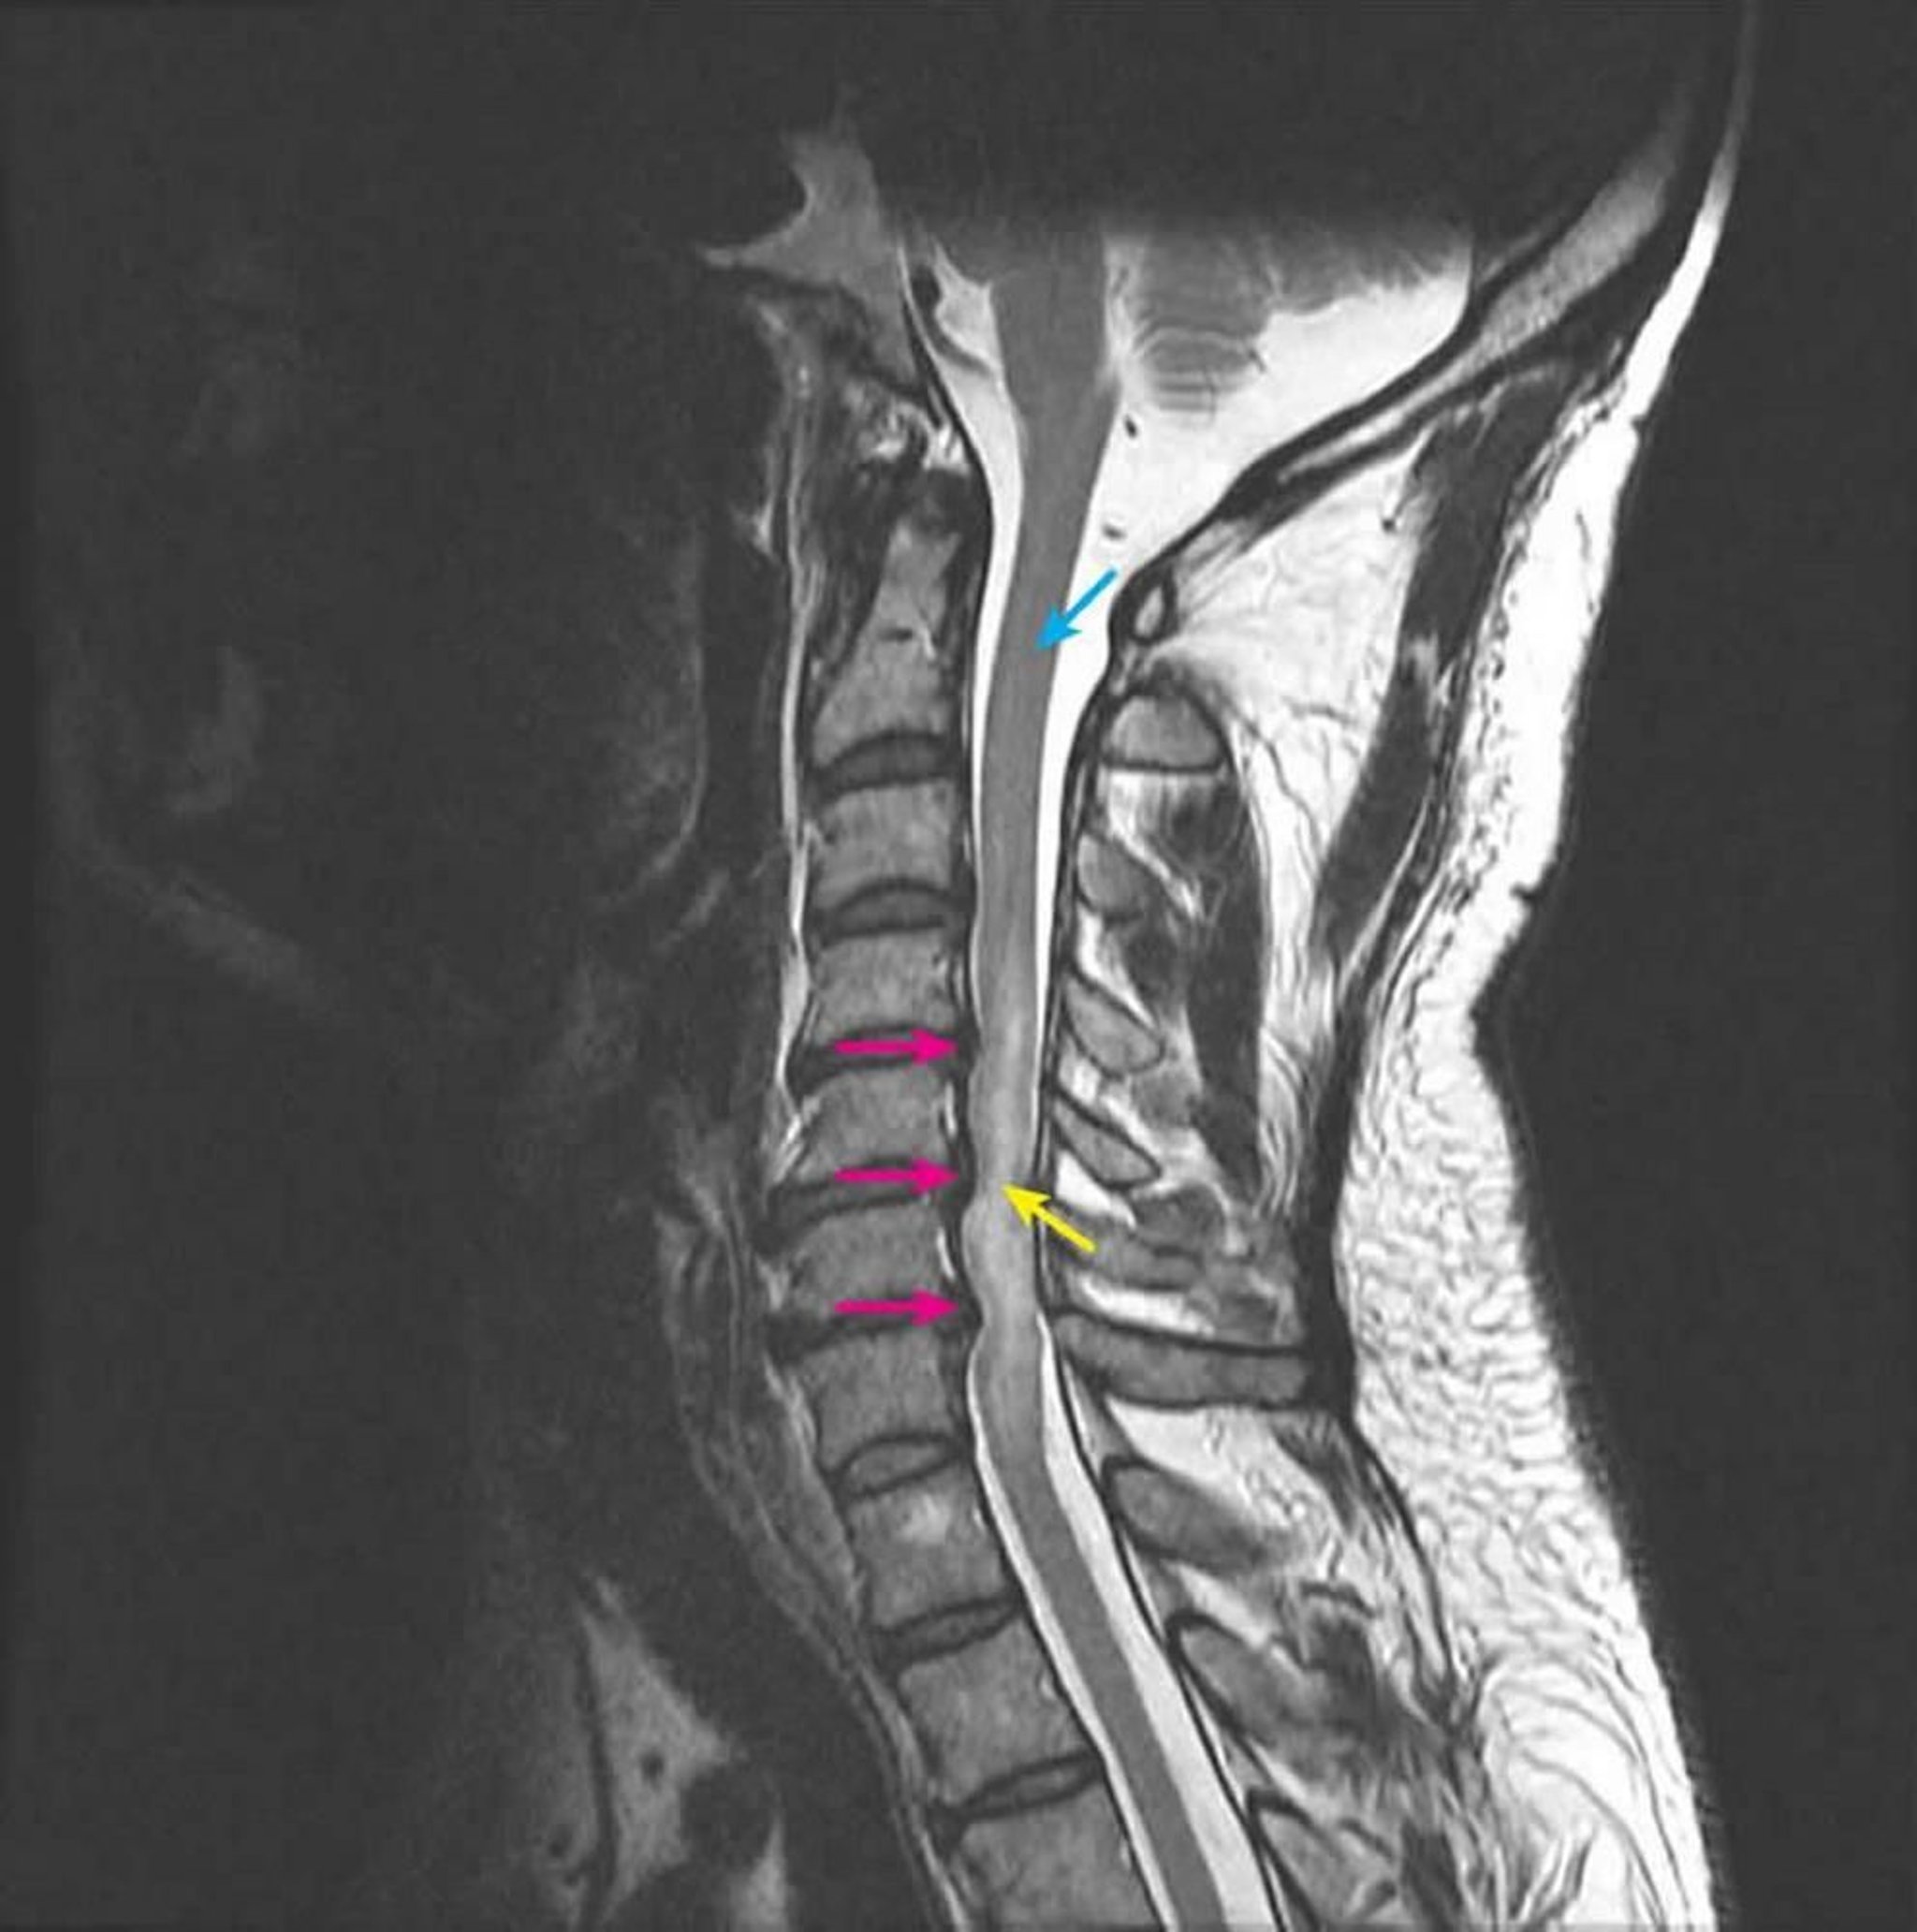

Mielopatía compresiva

La RM sagital en T2 muestra la compresión de la médula espinal en los niveles intervertebrales C4-5, C5-6, C6-7 secundaria a herniaciones discales posteriores en múltiples niveles (flechas rosas). La señal en T2 intramedular aumenta anormalmente, lo que representa el edema de la médula espinal (flecha amarilla). La señal de la médula espinal normal se ve en el nivel C2 (flecha azul).

Courtesy of John Tsiouris, MD, Division of Neuroradiology, New York–Presbyterian Hospital/Weill Cornell Medical Center.